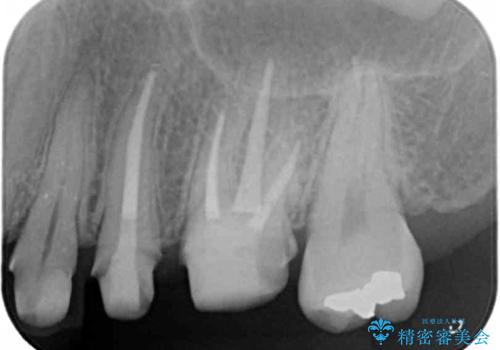

- 「笑った時に見えてしまう銀歯、古くなった修復物を白くきれいに治したい。」と希望され来院されました。

銀歯の下に再発していた虫歯を丁寧に取り除き、精密なセラミッククラウンで再治療を行います。

噛み合わせが強く、銀歯やクラウンは大きくする減ってしまっている状況でした。

噛み合わせをしっかり調整することで、安定した咬合関係を得ることができました。